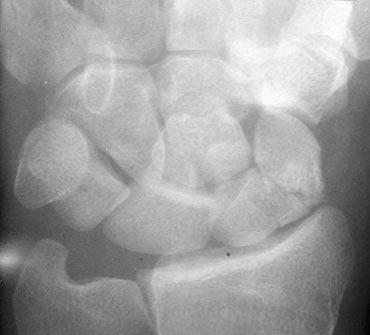

Trật khớp quanh nguyệt kèm gãy xương thuyền và mỏm trâm trụ. Đầu mặt lòng của xương nguyệt cũng bị gãy (xem vòng tròn).

Cùng ca lâm sàng với tư thế nghiêng được hiển thị thêm.

Bây giờ chúng ta thấy rõ ràng đây là trật khớp quanh nguyệt.

Vì vậy, hình dạng tam giác của xương nguyệt là kết quả của việc nghiêng đơn thuần.

Trên tư thế nghiêng, quan sát thấy gãy đầu mặt lòng của xương nguyệt. Do đó, bệnh nhân này có nguy cơ trật khớp tái phát.